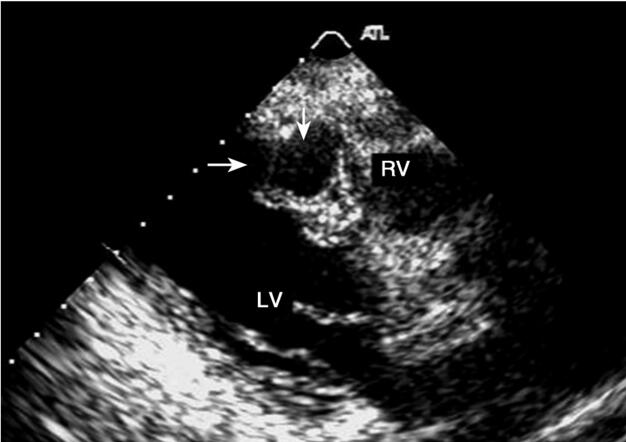

术后以“冠心病、急性心肌梗死(广泛前壁+高侧壁)、心律失常”收住CCU治疗。给予抗凝、抗血小板聚集、调脂、稳定斑块、扩冠、改善心肌微循环等对症治疗,并予替罗非班药物强化抗血小板。11日患者感胸闷、气短较前好转,但仍不能平卧。查体:BP 98/67mmHg,颈静脉充盈,双肺呼吸音粗,双中下肺可闻及少量细湿啰音,右肺呼吸音低,心界不大,心律不齐可闻及期前收缩。急查心电图:梗死对应导联ST段无明显回落 频发室性期前收缩 短阵室速。给予胺碘酮持续泵入并静脉推注硫酸镁2.5mg,但短阵室速再次出现并且为频发,给予面罩吸氧,静脉推注胺碘酮、地西泮5mg,后患者入睡。12日患者感病情好转,胸闷、气短较前减轻,可平卧,查体较前无明显改变。13日(入院第4天)突然胸闷、气短加重,双肺湿啰音较前增多,在胸骨左缘第3~4肋间出现响亮的收缩期杂音。急行床旁超声:提示广泛前壁心梗,室间隔穿孔(图1,彩图40)。

图1 室间隔穿孔(箭头)RV:右心室;LV是左心室